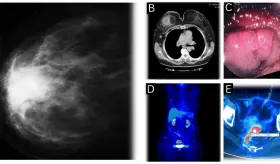

Este caso destaca la importancia de los estudios de imagen multimodales y plantea la necesidad de reconsiderar las estrategias de detección en mujeres no fumadoras, población en la que se observa un incremento creciente de esta neoplasia.